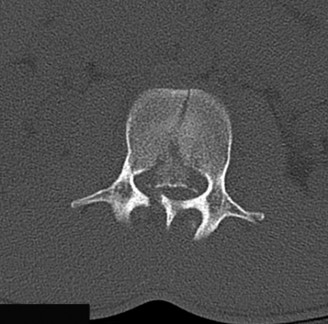

The options for definitive treatment of cervical facet dislocations? CASE 24 A 23-year-old man presents to your emergency room with severe back pain after a 30-foot fall out of a tree while intoxicated 3 hours earlier. He reports no neck pain, no upper extremity weakness or numbness, though he states that he feels weak in his legs and numbness in his groin. Currently, he is awake, alert, oriented, and cooperative and does not appear to be intoxicated. Vital signs included a blood pressure of 100/60 and heart rate of 95 beats per minute. Physical examination demonstrates midline tenderness of the lumbar spine with no palpable gap or step-off. Upper extremities show full strength and sensation. Lower extremities examination shows 2/5 bilateral strength in hip flexion and knee extension, 3/5 bilateral strength of ankle dorsiflexion, big toe extension, and ankle plantar flexion. Rectal tone is normal. Sensation to light touch and pin prick is diffusively decreased in both lower extremities and in the perineum. Bulbocavernosus reflex is present. A CT scan of his cervical and thoracic spine is negative. CT images of his lumbar spine are shown in Figures 1–32 and 1–33.

Figure 1–32

Figure 1–33

The injury of L2 is best described as which of the following?

Discussion

The correct answer is (B). The CT images reveal a comminuted fracture of the L2 vertebral body with involvement of its posterior aspect. The distinguishing feature between a burst fracture and a compression fracture is involvement of the posterior aspect of the vertebral body. Furthermore, burst fractures demonstrate that the posterior body fragments are no longer in continuity with the posterior elements (i.e., pedicles). Thus, they are free fragments that often are retropulsed into the spinal canal. Lamina fractures are often concomitant at the level of a burst fracture. By themselves, they do not infer injury to the posterior ligamentous complex. They can, however, be associated with dural tears and nerve root entrapment. Flexion–distraction injuries, also known as Chance or seat belt injuries, demonstrate widening of the posterior elements, either between the spinous processes, gapping at the facet joints, or through fractures in the posterior elements. There can be varying degrees of vertebral body compression, though typically not with comminution of the posterior vertebral margin. Fracture-dislocations can present with various

fractures of the anterior or posterior elements. The hallmark feature is a translation deformity that can be noted by misalignment of the vertebral bodies in the coronal and/or sagittal planes. A lumbar spine MRI is obtained, images from which are shown inFigures 1–34 and 1–35. Based on the information presented, the type of neurological injury is best characterized as which of the following? 1. Cauda equina injury

Figure 1–34

Figure 1–35

The correct answer is (A). The MRI demonstrates the L2 fracture with canal compromise. In this patient, the conus medullaris of the spinal cord terminates at the T12–L1 level. The fracture is at the L2 level. Thus, the neurological injury is at the level of the cauda equina, distal to the conus medullaris and spinal cord. The patient’s neurological examination is consistent with this type of injury with the presence of lower extremity weakness, intact rectal tone, and perineal numbness, though this can vary.